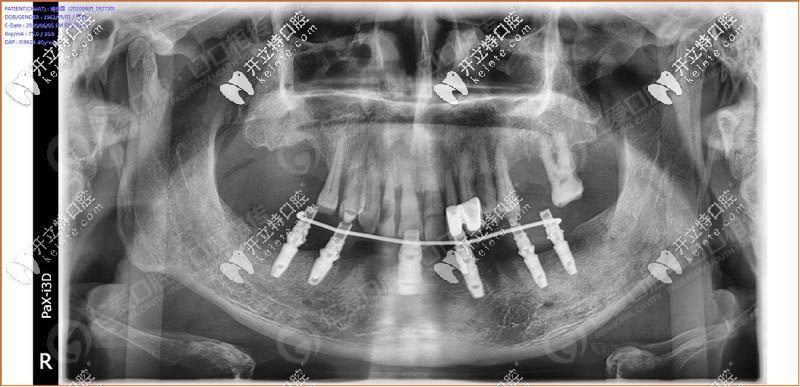

經(jīng)過我院種植醫(yī)生面診,拍片檢查發(fā)現(xiàn),31、32 、33、 34顆牙松動(dòng)(3度),43顆牙也松動(dòng)了, 44、45多年前做了烤瓷牙修復(fù),其余牙缺失。

具體設(shè)計(jì)方案:拔除下半口松動(dòng)牙后,在33、34、36、43、44、46牙窩采用種植導(dǎo)板植入性價(jià)比高的登騰種植體,當(dāng)天帶上牙冠,實(shí)現(xiàn)“當(dāng)天種牙,當(dāng)天用”。

順利植入6顆種植體后,把過渡性臨時(shí)假牙固定到下頜的種植體上實(shí)現(xiàn)了當(dāng)天種牙,當(dāng)天用的即刻負(fù)重種植牙。